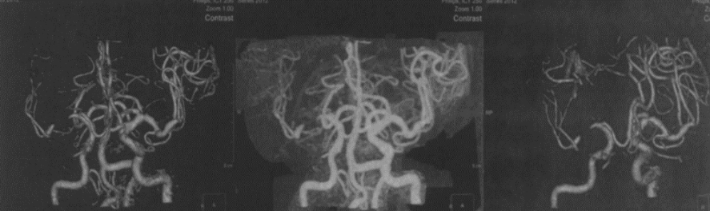

2020年9月起,患者自诉头晕、偶有左侧肢体乏力,复发CTA(2020-10-25)提示MCA无明显再狭窄,与1年前比较无变化

DSA检查与2019-10比较无明显变化